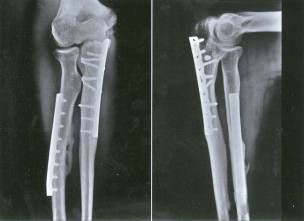

Определить характер травмы насилием

Высокоэнергетическая травма часто сопровождается тяжелым повреждением мягких тканей.Он характеризуется отеком конечностей, образованием волдырей, ссадин и разрывов кожи.Операцию следует отложить на это время.При этом необходимо исключить синдром фасциального пространства и повреждения сосудов и нервов.

Особенность анатомии – важность покрытия мягкими тканями.

Ранняя стадия: в течение 8 часов

Внешний фиксатор считается первым выбором для раннего лечения.

Гипсовая опора

Вытяжение пяточной кости

Фаза II: около 2 недель.